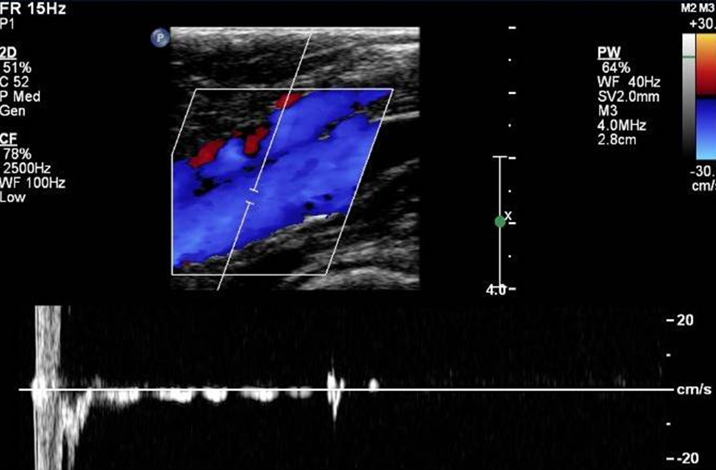

what does this show

normal distal augment

normal